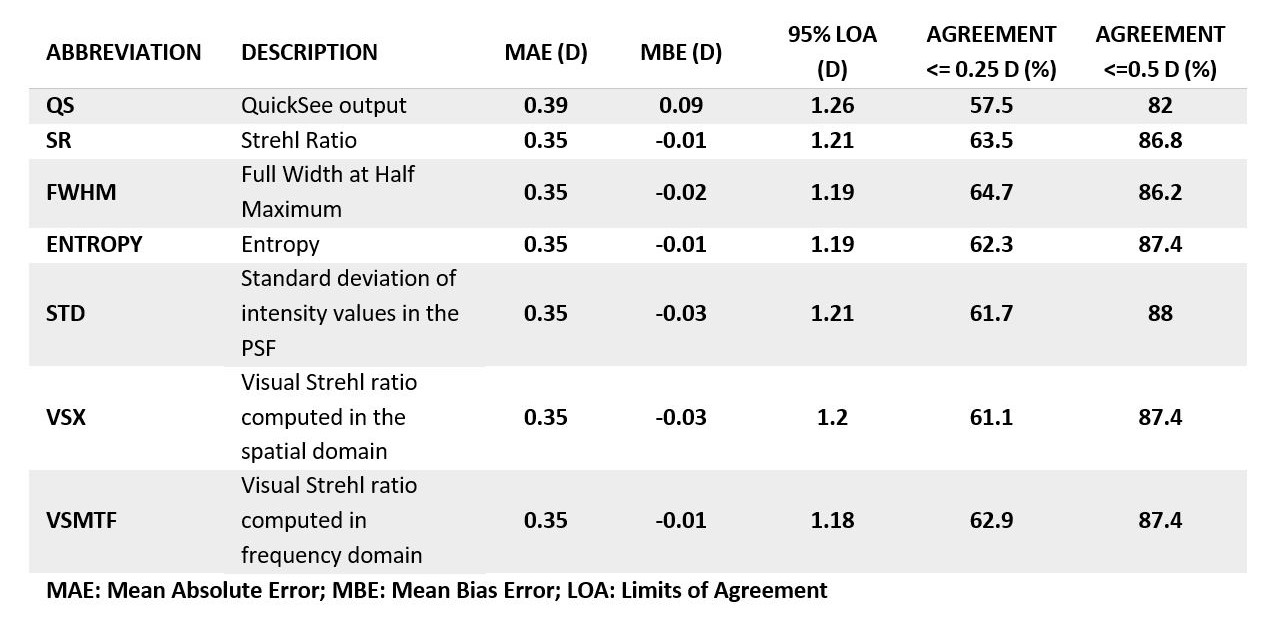

PurposeModern autorefractors have demonstrated high accuracy and higher repeatability than manifest refraction in adults yet are not considered precise enough to substitute the gold standard, even in low-resource settings where there is a severe shortage of experienced refractionists. This work evaluates a novel approach that combines dynamic wavefront aberrometry data, acquired using an affordable portable autorefractor, with the analysis of retinal image quality metrics (IQMs) to predict subjective refraction. Methods56 subjects (34±14 years) were recruited for the analysis. Each participant underwent standard clinical refraction followed by a 10-second video acquisition using a QuickSee (QS) wavefront aberrometer (PlenOptika, USA). Shack-Hartmann images of each video for the right eye were processed to obtain Zernike coefficients up to the 4th order. Coefficients obtained for each image were mathematically corrected with the closest sphero-cylindrical correction and the residual wavefront error was used to calculate the Point Spread Function (PSF) and IQMs (e.g., Strehl Ratio) describing some performance parameter of the corrected eye. Since each IQM is part of a dynamic sequence, it is possible to build a dynamic signal for each metric which contains information about fluctuations in image quality during the measurement. The final refraction is obtained as the average of the refractions corresponding to the images whose IMQs provided optimal performance. ResultsThe proposed method reduced the differences between QS and manifest refraction. Specifically, for spherical equivalent refraction (M) (Table 1) a 79% average reduction in MBE together with moderate average improvements for MAE (10.3%), LOA (5%), and percentage of agreement within 0.25D (8.8%) and 0.5D (6.3%) were found for all IQMs evaluated. ConclusionsThe proposed algorithm behaves as an efficient filter which selects those measurements within the dynamic sequence that are more representative of the manifest refraction of the patient. |

PurposeHigh repeatability portable autorefractors may enable effective deploy of global-health initiatives to mitigate uncorrected refractive error worldwide. For example, in studies to evaluate the effectiveness of different measures, repeatability has a direct impact on the statistical power and sample size required, while in screening applications, contributes to increased sensitivity and specificity. This work presents a preliminary assessment of the inter- and intrasession repeatability of an affordable autorefractor (QuickSee, PlenOptika Inc) under two separate measurement conditions, with and without fogging lenses. Methods6 volunteers (29,8 ± 8,1 years old) were measured at 2 different sessions spaced 1-week. Each subject was tested 6 times per session with the QuickSee, 3 times in standard mode and 3 using a modified version of the device eyecup to allow over-refraction through fogging lenses (+2.0 D). Intersession measurements were spaced 5 minutes apart and the complete alignment procedure was repeated for each measurement. After converting autorefractor readings into power vectors (M, J0, J45), repeatability was evaluated using the Bland-Altman method to compare differences between all possible combinations from each subject (inter- and intrasession). Repeatability coefficients (RPC), estimated as the 95% limits of agreement, and the mean absolute errors were also evaluated. In all cases, only results for the right eyes were analyzed. ResultsParticipants had an average Spherical Equivalent (SE) refraction of -0.75 ± 2.06 D, (Min -5.11 D, Max 0.175 D). A total of 36 samples per dataset were obtained for the intrasession analysis while 54 samples per dataset were used in the intersession comparison. In all cases the mean difference was practically 0 indicating no bias for any of the vector components. SE RPCs for intrasession test were 0.15 D in standard mode and 0.29 D with the fogging lenses. Intersession RPCs were 0.29 D and 0.4 D without and with the fogging lenses, respectively. Detailed results for all vector components are shown in Table 1. ConclusionsThis preliminary analysis shows that the device can provide excellent RPCs in standard mode, which decrease moderately with the use of the fogging lenses. Further work exploring improvements in the eyecup design and measurement averaging techniques may further enhance the RPC values in over-refraction mode. |